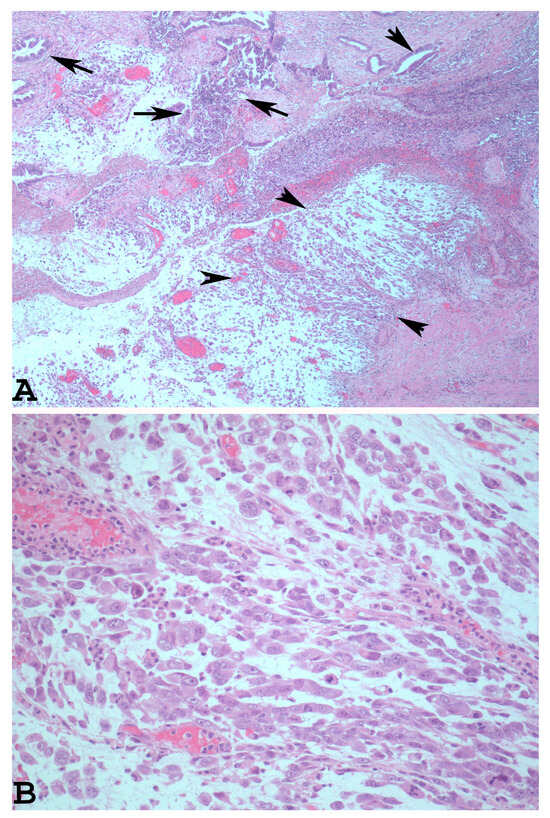

1.2. The Main Morphological and Immunohistochemical Features of EDC Used for Correct Pathological Diagnosis